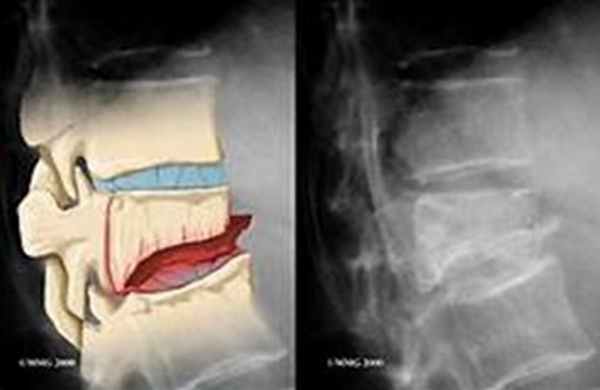

Рентгенограмма при компрессионном переломе позвонка с латеральной компрессией

Единичные переломы позвонков на уровне выше T4 свидетельствуют о злокачественном поражении, а не об остеопорозе. Если данных за остеопороз нет, следует провести двухэнергетическую рентгеновскую абсорбциометрию (DXA). Если остеопороз диагностирован недавно, необходимо провести исследование для выявления факторов, индуцирующих развитие вторичного остеопороза Другие виды исследований Остеопороз – прогрессирующее метаболическое заболевание кости, при котором происходит снижение ее минерализации (массы костной ткани на единицу объема), сопровождающееся нарушением ее структуры. Прочитайте дополнительные сведения После значительной травмы проводят КТ, чтобы оценить состояние всех отделов позвоночника, а при наличии неврологических дефицитарных или продуктивных симптомов - МРТ Магнито-резонансная томография Сагиттальное Т1-взвешенное изображение головного мозга показывает, что срединные структуры без изменений. Сагиттальное взвешенное по протонной плотности 3-тесла магнитно-резонансное изображение. Прочитайте дополнительные сведенияРентгенограмма при компрессионном переломе позвонка с латеральной компрессией

Рентгенография

Это стандартное исследование для диагностики компрессионных переломов позвоночника. Для полноценной диагностики необходимо проведение передних и боковых снимков. Возможно также проведение снимков со сгибанием и разгибанием для определения грубой нестабильности.